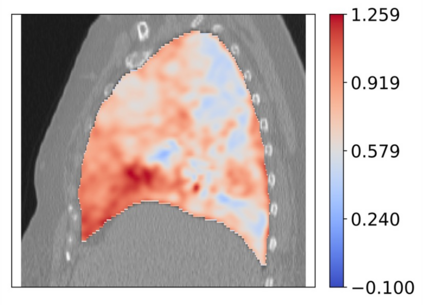

Deformable image registration is a fundamental task in medical image analysis and plays a crucial role in a wide range of clinical applications. Recently, deep learning-based approaches have been widely studied for deformable medical image registration and achieved promising results. However, existing deep learning image registration techniques do not theoretically guarantee topology-preserving transformations. This is a key property to preserve anatomical structures and achieve plausible transformations that can be used in real clinical settings. We propose a novel framework for deformable image registration. Firstly, we introduce a novel regulariser based on conformal-invariant properties in a nonlinear elasticity setting. Our regulariser enforces the deformation field to be smooth, invertible and orientation-preserving. More importantly, we strictly guarantee topology preservation yielding to a clinical meaningful registration. Secondly, we boost the performance of our regulariser through coordinate MLPs, where one can view the to-be-registered images as continuously differentiable entities. We demonstrate, through numerical and visual experiments, that our framework is able to outperform current techniques for image registration.